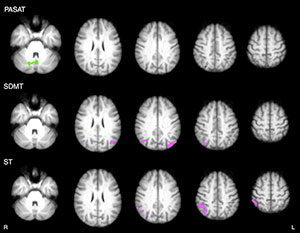

Figure 4. Axial statistical maps show differences in thalamic FC at follow-up in intervention group compared with that in wait-list group. Purple areas represent higher FC increase in intervention group (posterior cingulate gyrus, precuneus, and lateral parietal cortex, bilaterally). Green areas represent lower FC increase in intervention group (vermis, cerebellar hemispheres and left dorsal-lateral prefrontal cortex).

Figure 5. Axial statistical maps show areas of significant correlations between posttraining thalamic FC and neuropsychological score changes in intervention group. Purple areas represent positive correlations (bilateral parietal cortex for SDMT, right parietal cortex for ST) green areas show negative correlations (vermis and right cerebellar hemisphere for PASAT).